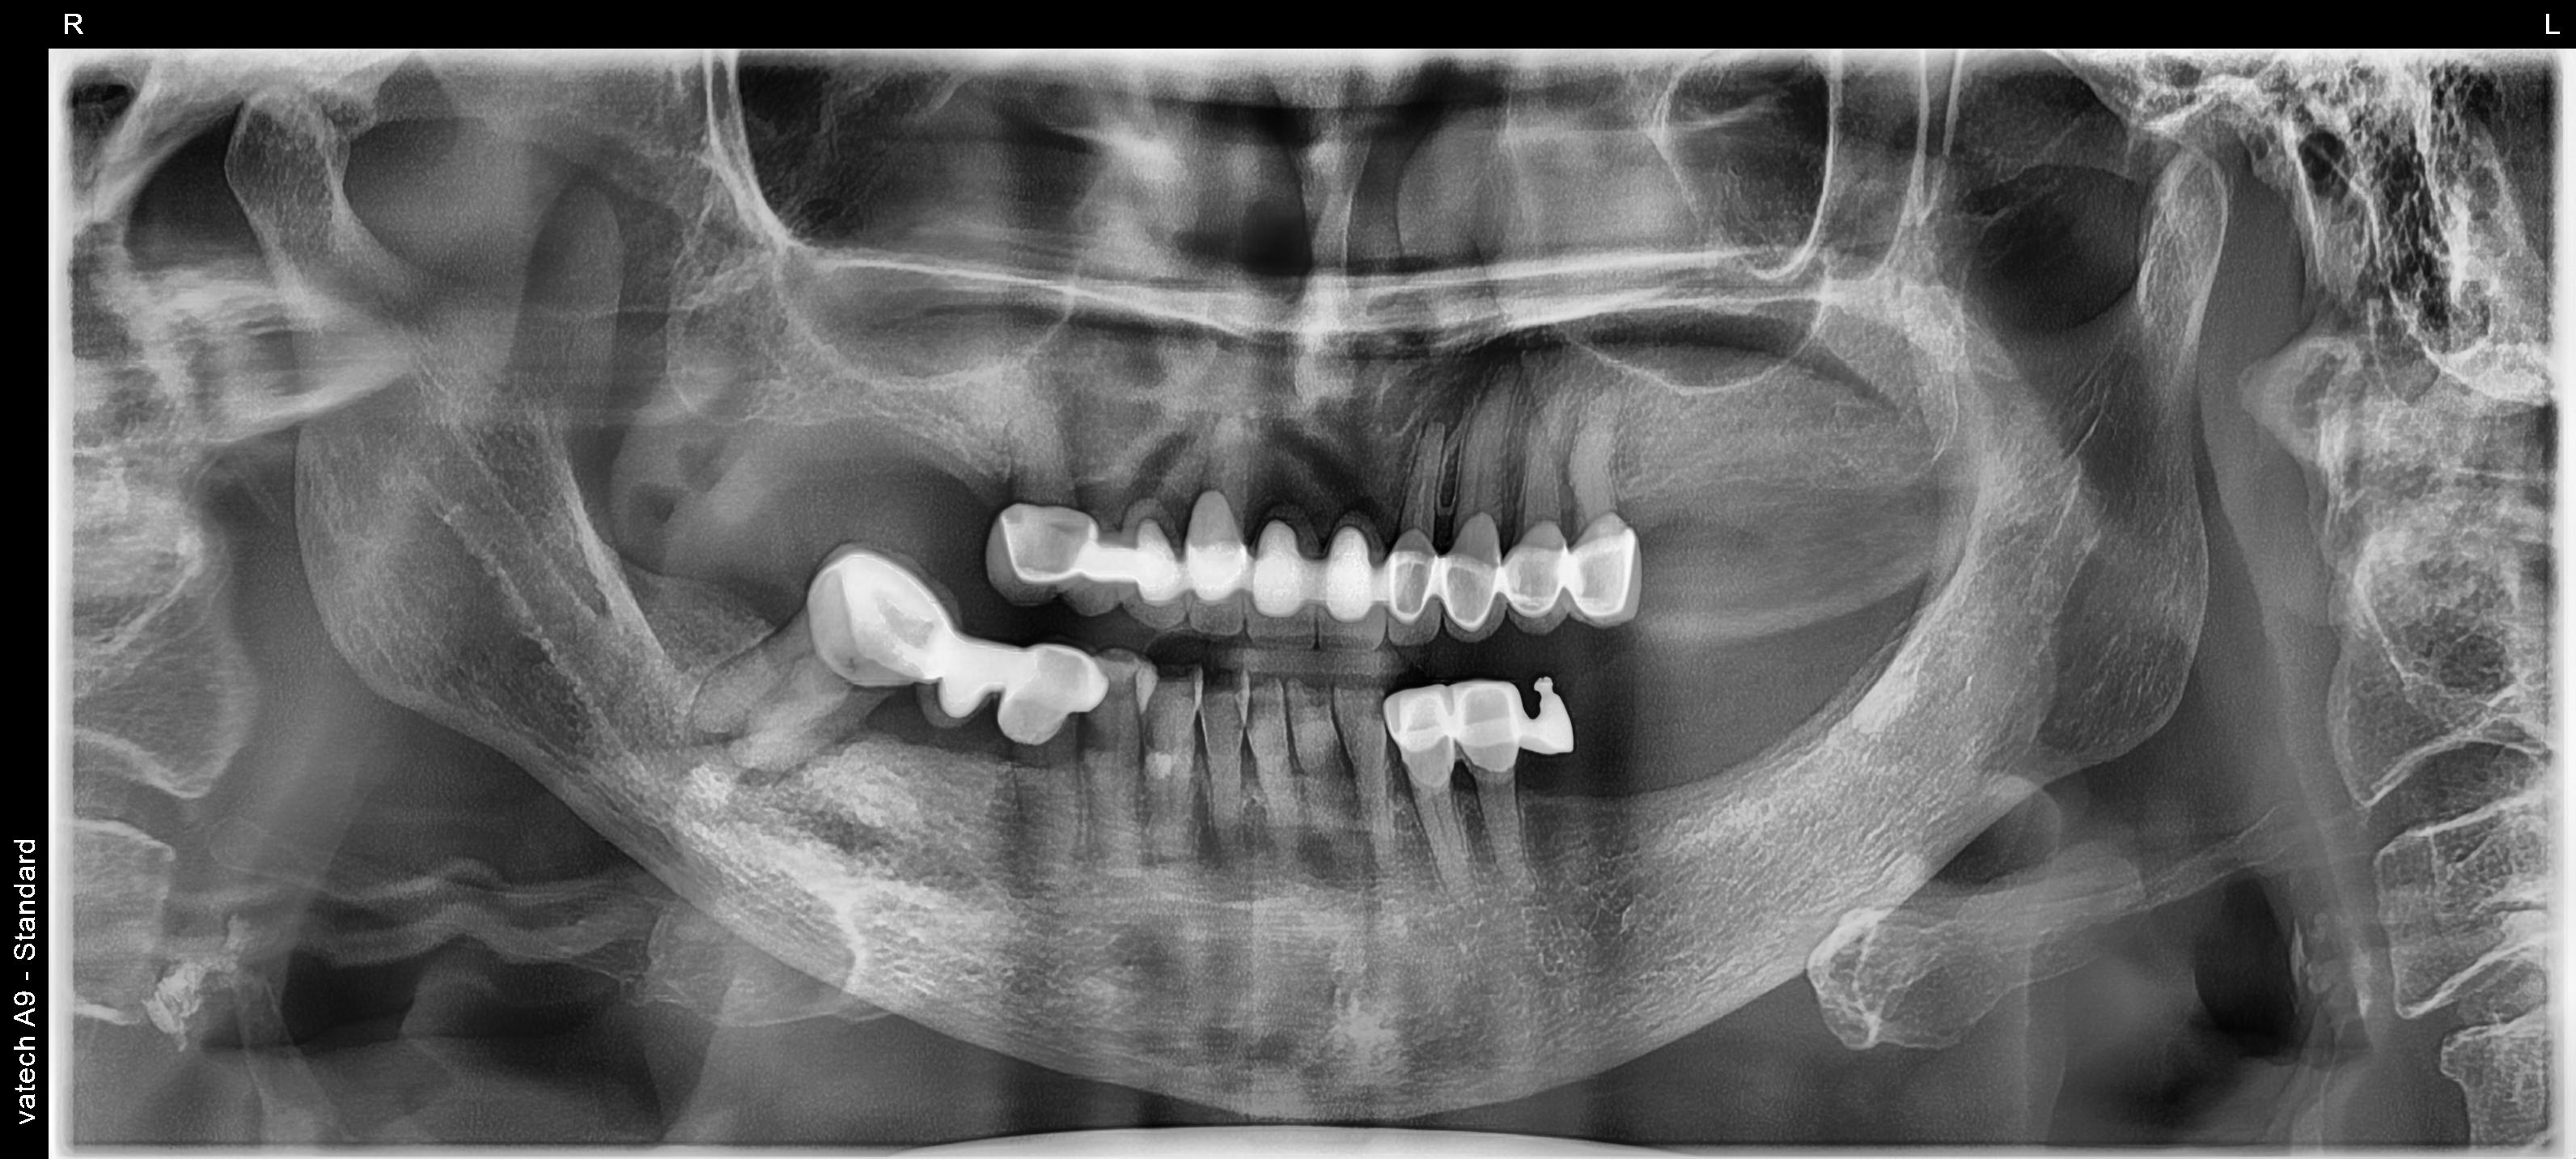

Edit Record Check our patient data records. Add patient information Patient Info Profile picture Last Name First Name Middle Name Birthdate Age Street Barangay City Country Zip Code Contact number Email Procedure 08/08/25 consultation for CROWN 10/01/25 impression for temporary crown 10/07/25 fixed bridge 25 to 15 shade cervical A3, A2 body, incisal shade 10 units material zirconia 10/14/25 installation of crown 10 units zirconia 10/22/254- exo 47 with suture and gel foam prep : • Tooth #44-45-46-Cantilever • Tooth #33-34-35-Cantilever Individual Crown Tooth #41-42-43-31-32 shade A2-A3 lab: vintage/ vvramxx FREE: LC WITH CAOH #45 WITH FIBER, #12 POST AND CORE BUILD UP WITH FIBER POST, LC #22 DISTAL/LINGUAL, #21 MESIAL DISTAL 10/29/25 installation of zirconia crown (lower) 11 units 11/11/25 recall/ removal of premature contact on quadrant 1 and 4 File px20250802_144401_4975_27858872_ma_ligaya_liwanag.jpeg File 2 ma_ligaya_liwanag_1.docx File 3 mrs_liwanag.docx File 4 File 5 File 6 File 7 File 8 File 9 File 10 File 11 File 12 File 13 File 14 File 15 File 16 File 17 File 18 File 19 File 20 Retain Record Retain Record Yes No Save Your Changes